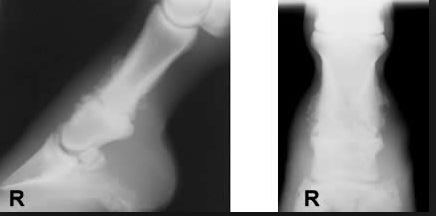

Here are some examples of ring bone (random pics from a google image search)

Nasty eh?